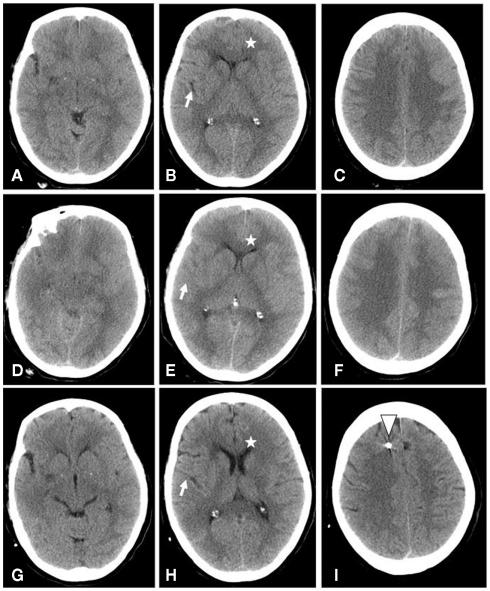

We report a 57-year old female patient with a rapid and dramatic dynamic of whole brain edema caused by tuberculous meningitis. After initiation of tuberculostatic medication, general condition of the patient worsened and finally she was intubated due to a progredient loss of consciousness and respiratory insufficiency. Repeated cerebral computer tomography (CCT) revealed a global brain edema with slit ventricles and a dramatic progress of generalized brain swelling. Highly interesting, a rapid expanded regime of brain pressure monitoring and treatment according to a neurosurgical intensive standard ICP/CPP management protocol, which was complemented by the tuberculostatic therapy and high dose steroid application, dramatically improved the general conditions, so that the patient is now in a general condition which corresponds that before the occurrence of tuberculous meningitis. Thus, it is mandatory in situations with a rapid progressive brain swelling caused by bacterial meningitis to consider an intensified cerebral monitoring and stratified treatment protocol in order to avoid the devasting effects of a long lasting increase in intracranical pressure.

我们报告了一例 57 岁女性患者,因结核性脑膜炎导致全脑迅速而剧烈的水肿。在开始抗结核治疗后,患者的一般情况恶化,最终因意识逐渐丧失和呼吸功能不全而插管。反复的脑部计算机断层扫描(CCT)显示出弥漫性脑肿胀,脑室狭窄,脑肿胀迅速进展。有趣的是,根据神经外科强化标准的颅内压(ICP)/脑灌注压(CPP)管理方案,快速扩展的脑压力监测和治疗方案,再加上抗结核治疗和大剂量类固醇的应用,显著改善了一般状况,使患者的一般状况恢复到结核性脑膜炎发生前的水平。因此,对于由细菌性脑膜炎引起的快速进行性脑肿胀,必须考虑强化的脑监测和分层治疗方案,以避免颅内压长时间升高带来的破坏性影响。